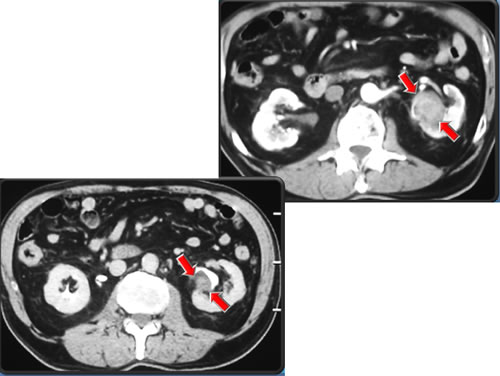

СКТ

Кисты обеих почек, размерами от 16 х 18 мм до 33 х 33 мм. В верхнем полюсе левой почки – киста 47 x 51 мм. В среднем сегменте левой почки – образование, неоднородной структуры, с четкими, неровными контурами, размером 31 x 35 мм.